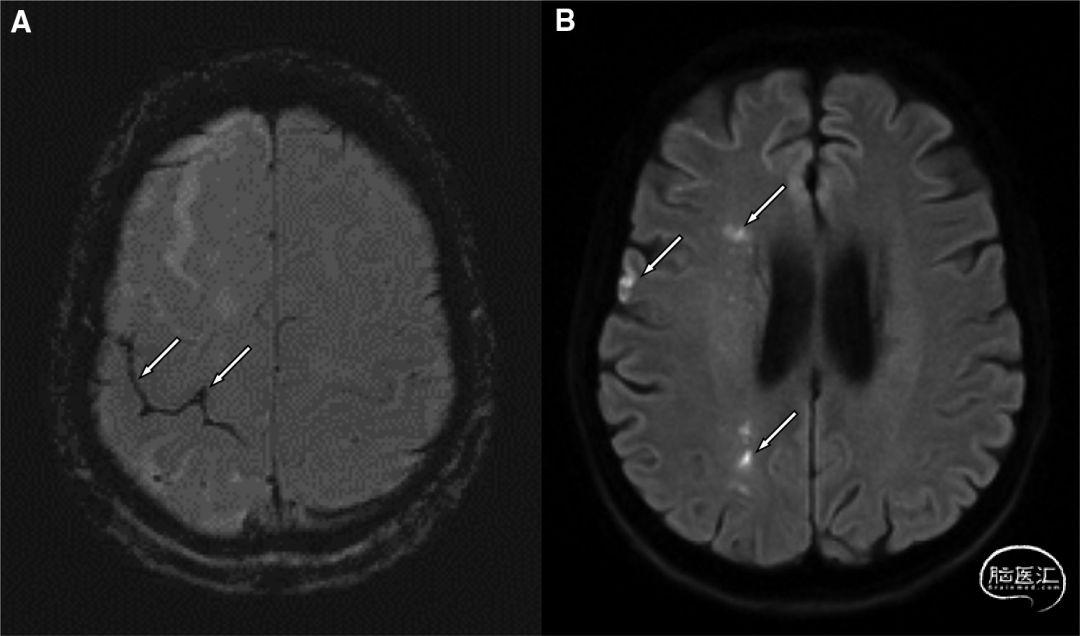

术后磁共振成像显示边缘带梗死,并证实蛛网膜下腔出血无进展(图2)。临床结局非常好(3个月改良Rankin量表=1)。